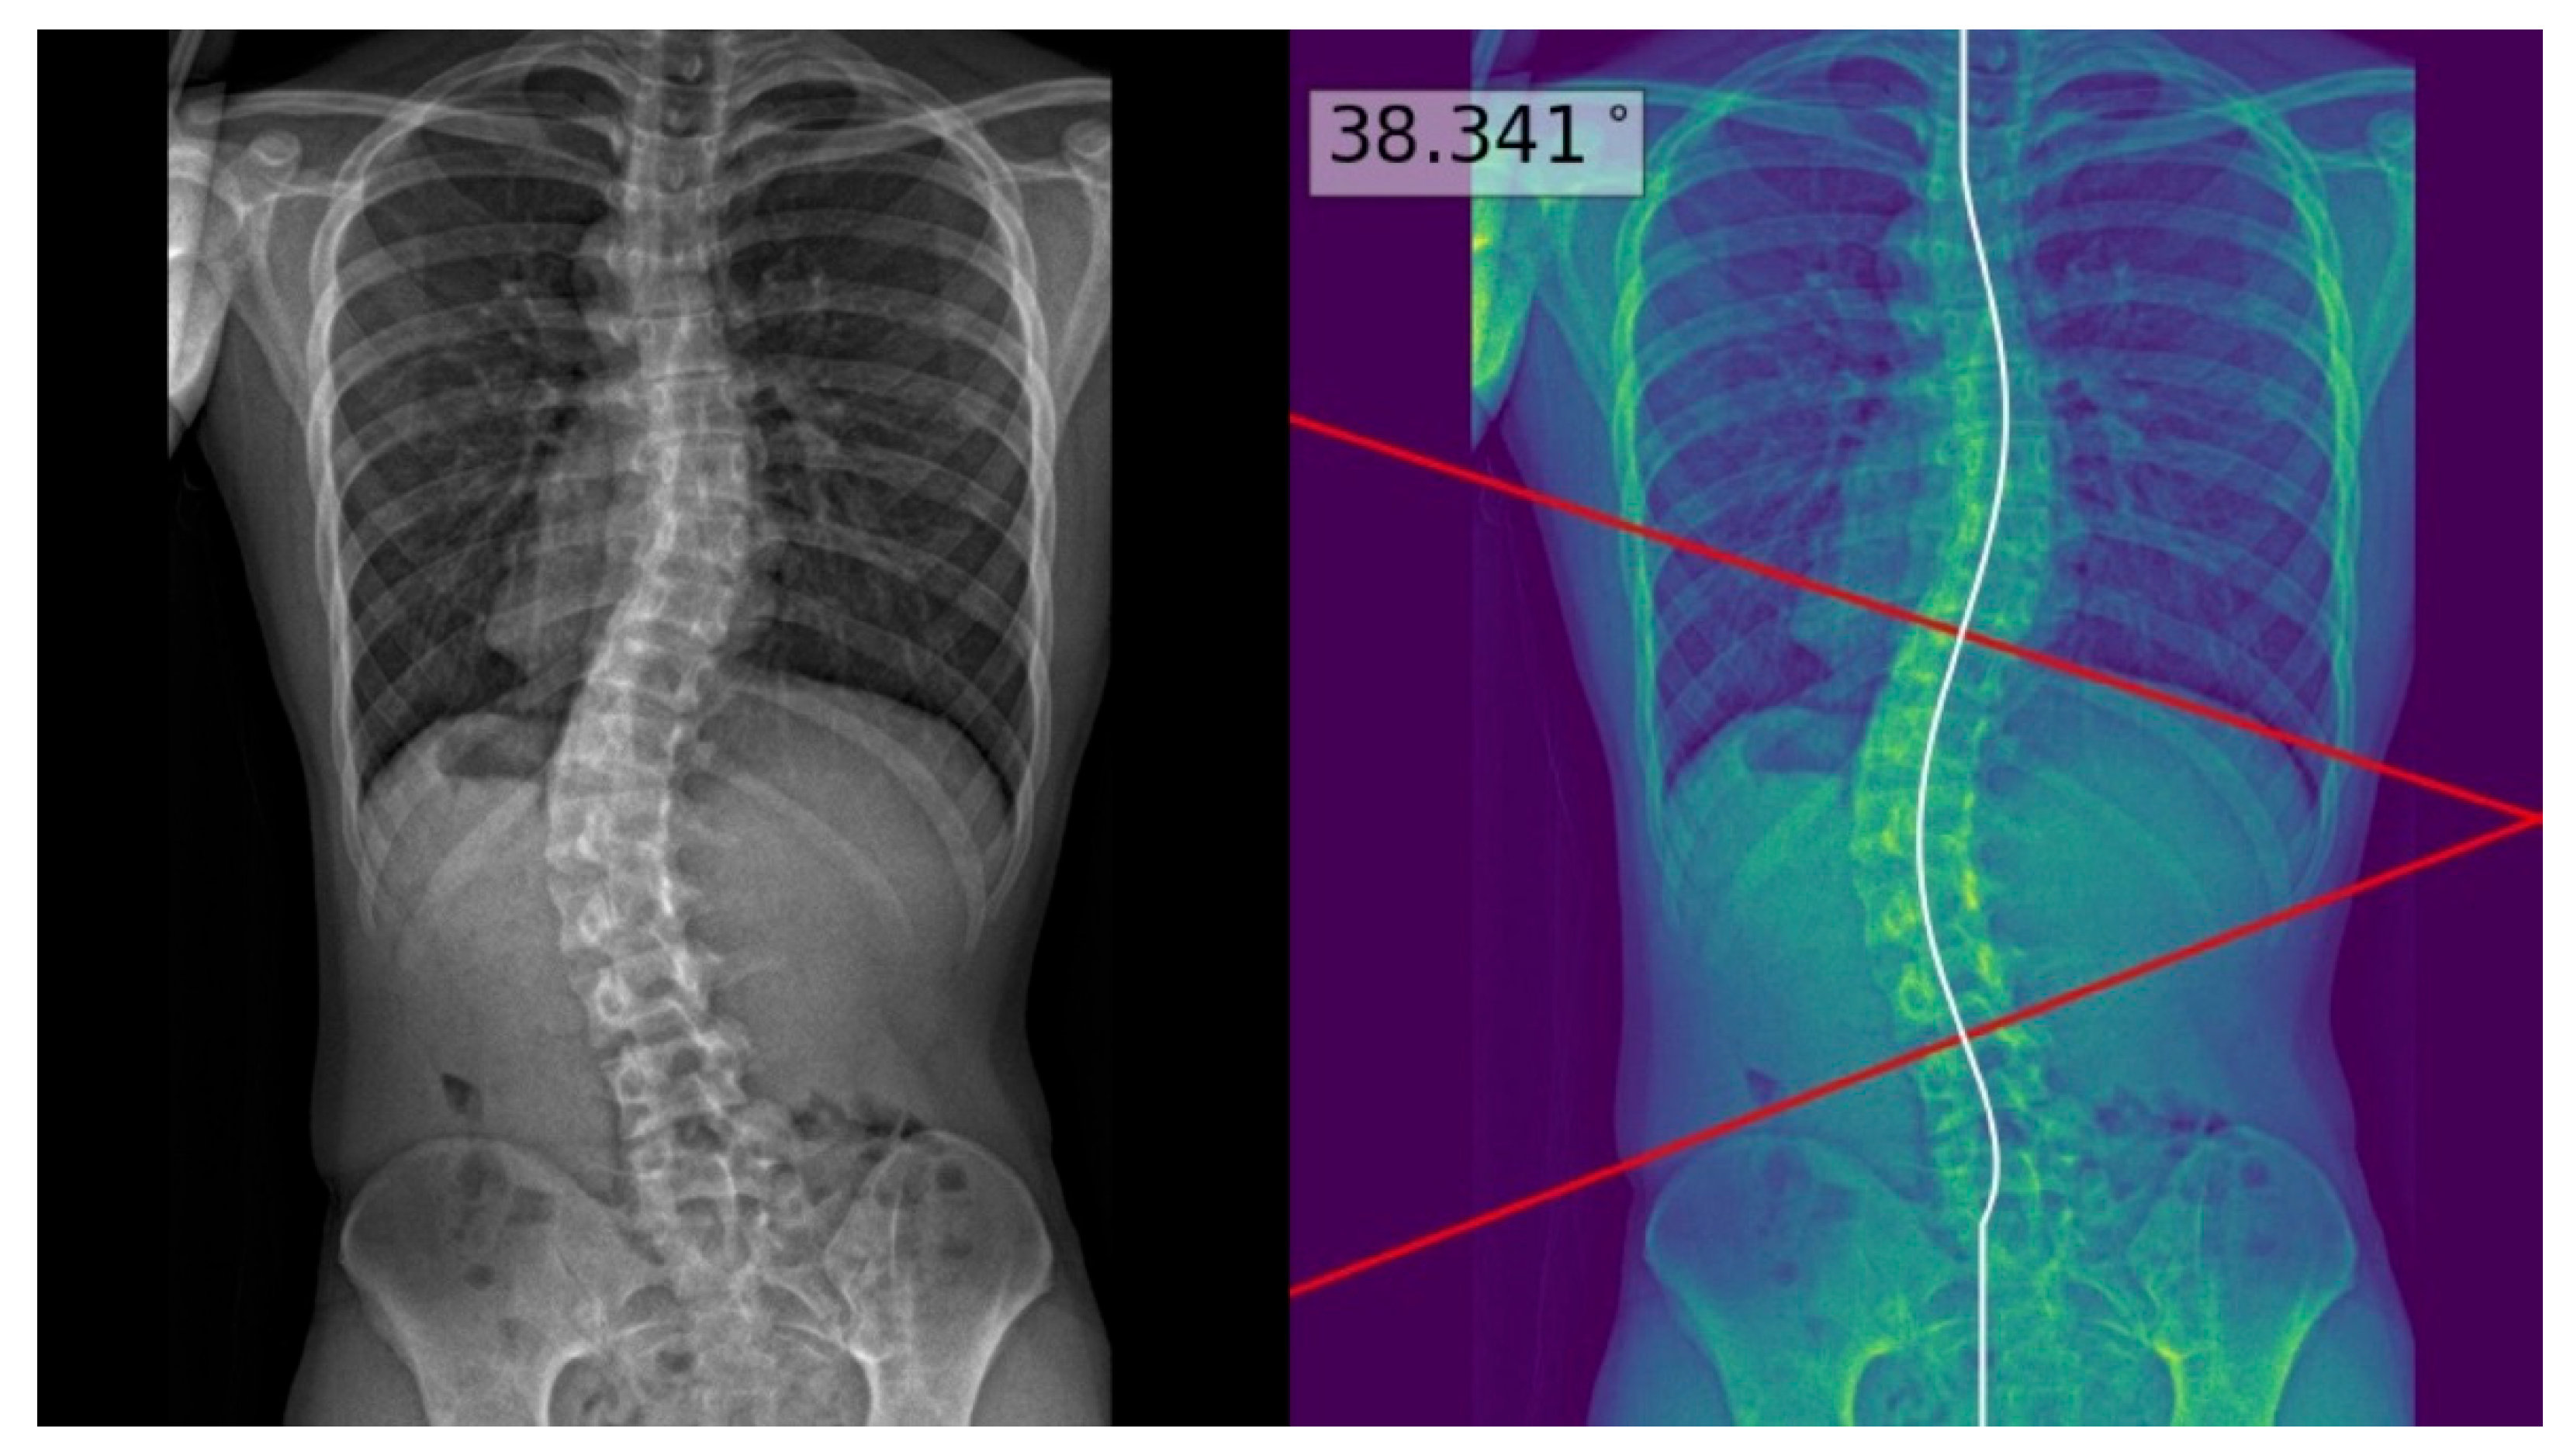

Radiographic evaluation of suspected scoliosis is crucial for diagnosis and further management [5]. On a standing posteroanterior spinal radiograph, scoliosis is defined as a coronal curvature with a Cobb’s angle of 10 degrees or greater [6]. Figure 1 illustrates an example of the measurement of Cobb’s angle, which refers to the greatest angle between two lines passing through the superior and inferior endplates of two appropriately selected vertebrae. The severity of AIS is classified according to the angle of the major coronal curve, with curves of approximately 10–24°, 25–40° and >40° representing mild, moderate and severe scoliosis, respectively [7,8]. This classification is essential for prognostication and treatment planning [9,10].

The process above allowed deep learning model masks of the whole spine (showing individual vertebrae) to be obtained and compared to the manual annotations. The model achieved a Dice similarity coefficient of 0.88 and Intersection over Union (IOU) of 84% on validation; it achieved a Dice coefficient of 0.619 and IOU of 72% on testing. Using the masks, the deep learning model determined the center of each vertebra, and extrapolated a polynomial curve along the centers. The spline technique, or the exhaustive assessment of the maximum angles between the vertebrae center line pairs to determine the largest angle, was the method of choice for the measurement of Cobb’s angle. Once the model has identified the correct points on the line, the reader could view the model prediction as extended lines and text in the top right hand corner of the image. For physicians’ review and augmentation, the model (available at the following web server: https://radweb.sha.endeavour-poc.ai/, accessed on 1 May 2022) annotated the largest possible angle in the output images, as shown in Figure 2 and Figure 3. Appendix A provides more details on the deep learning model.

The readers performed manual measurements of the major coronal curve angle without assistance from the deep learning model using the digital angle tool on the Picture Archiving and Communication System (PACS) (Centricity, GE Healthcare, Chicago, IL, USA), with the results overlaid on the images. When interpreting the radiographs with assistance from the deep learning model, the readers accessed the automated major coronal curve calculations and annotations overlaid on the images (as illustrated in Figure 2 and Figure 3). The readers could accept the model predictions or perform manual calculations using the same digital tool as per their clinical judgment, especially if the center curve alignment did not match the image.

Figure 1. An example of Cobb’s angle, measured by a deep learning model (utilized in this study). The angle of the major coronal curve (i.e., Cobb’s angle) refers to the greatest angle between two lines passing through superior and inferior vertebral endplates. Proper vertebral endplate selection is crucial to allow the accurate measurement of Cobb’s angle, but remains challenging for inexperienced readers.

Figure 2. Posteroanterior whole-spine radiograph for scoliosis assessment (left) with the deep learning model predictions overlaid on the processed image (right). The deep learning model extrapolated a polynomial curve along the centers of the vertebrae, and highlighted the predicted Cobb’s angle for the reader at the maximum angulated curve. This is an example of a good model prediction, with less than three degrees of difference from the reference standard.